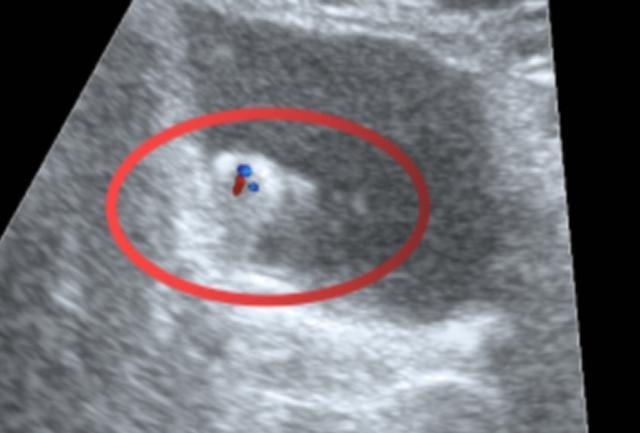

泌尿系超声结果显示:

(▲彩色多普勒显像:结节内可见点条状血流信号)

超声诊断意见:膀胱壁占位性病变,建议进一步检查。